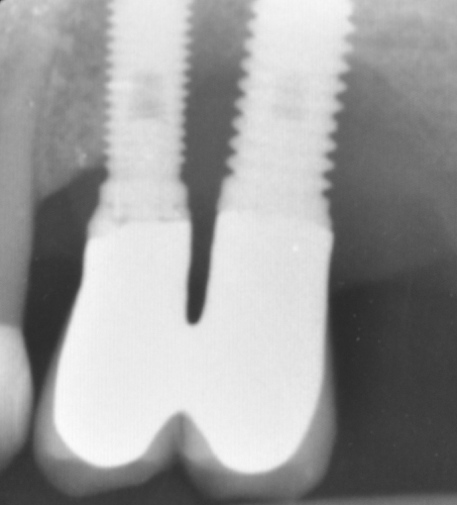

The parameters used to define peri-implant disease usually are: Probing Depth (PD), Crestal Bone Loss (CBL), Bleeding on Probing (BOP) and presence of suppuration and/or fistula.9 Peri-implant mucositis is characterised by soft tissues inflammation witnessed by BOP with or without PD deepening but no effects on the crestal bone while peri-implantitis is characterised by CBL, BOP alone or in conjunction with pus, with or without PD deepening. (Figs. 1, 2 and 3) display the diagnostic steps of a case of peri-implantitis. While mucositis allows a complete healing, peri-implantitis is not reversible.12

Crestal Bone Loss sets another ambiguous point because an adaptive change of the marginal bone level is known to occur afterimplantplacement and restoration.1It’s necessary to agree a baseline for the radiographic evaluation of bone level changes and set an acceptable bone loss rate. Basing on longitudinal clinical studies, it’s rational to chose the time of prosthesis installation as a reference from which the disease can be diagnosed and followed.14 Basing on Albrektson and Zarb review, 1.5mm of bone loss in the first year and less than 0.2mm annually are considered success criteria.1 A CBL exceeding this rate testifies the risk of implant failure. Don't forget that intra-oral x-rays allow to evaluate the interproximal bone level only, missing an appropriate vision of the buccal/lingual sides, where probing becomes essential. Bleeding on Probing is the key parameter for peri-implant disease diagnosis.13 Presence of BOP can be found in 91% of implants with peri-implantitis and its absence is regarded as a reliable predictive parameter of implant health.12

Fig.3: Case 1. X-ray testifying severe peri-implant CBL.

So far, there is no scientific evidence supporting the efficacy of this coadjuvant. The tested protocol consist of a Multiple Anti Infective Non Surgical Therapy (MAINST) that involves the use topical 14% doxycycline to solve the peri-implantitis acute phase and, after 7 days, a session of Full Mouth Air Polishing Therapy (FM-EPAPT) through erythritol powder (Fig.7), a piezo-ceramic device with a PEEK tip (Fig.8), the curettage of internal pocket line (Fig.9) and a second application od Doxy. The patients were further followed with quarterly maintenance sessions carried on with the same FM-EPAPT protocol. Up to 12 months BOP and mean PD decreased significantly and successfully, accompanied by a gain of attachment level up to 12 months. The first case-series about MAINST is waiting to be published and the results are encouraging. Figure 10 and 11 show the healing at 6 and 12 months after MAINST protocol of the peri-implantitis case displayed at the beginning of this article (Fig.1,2,3,4) and figure 12-21 show a complete MAINST case.